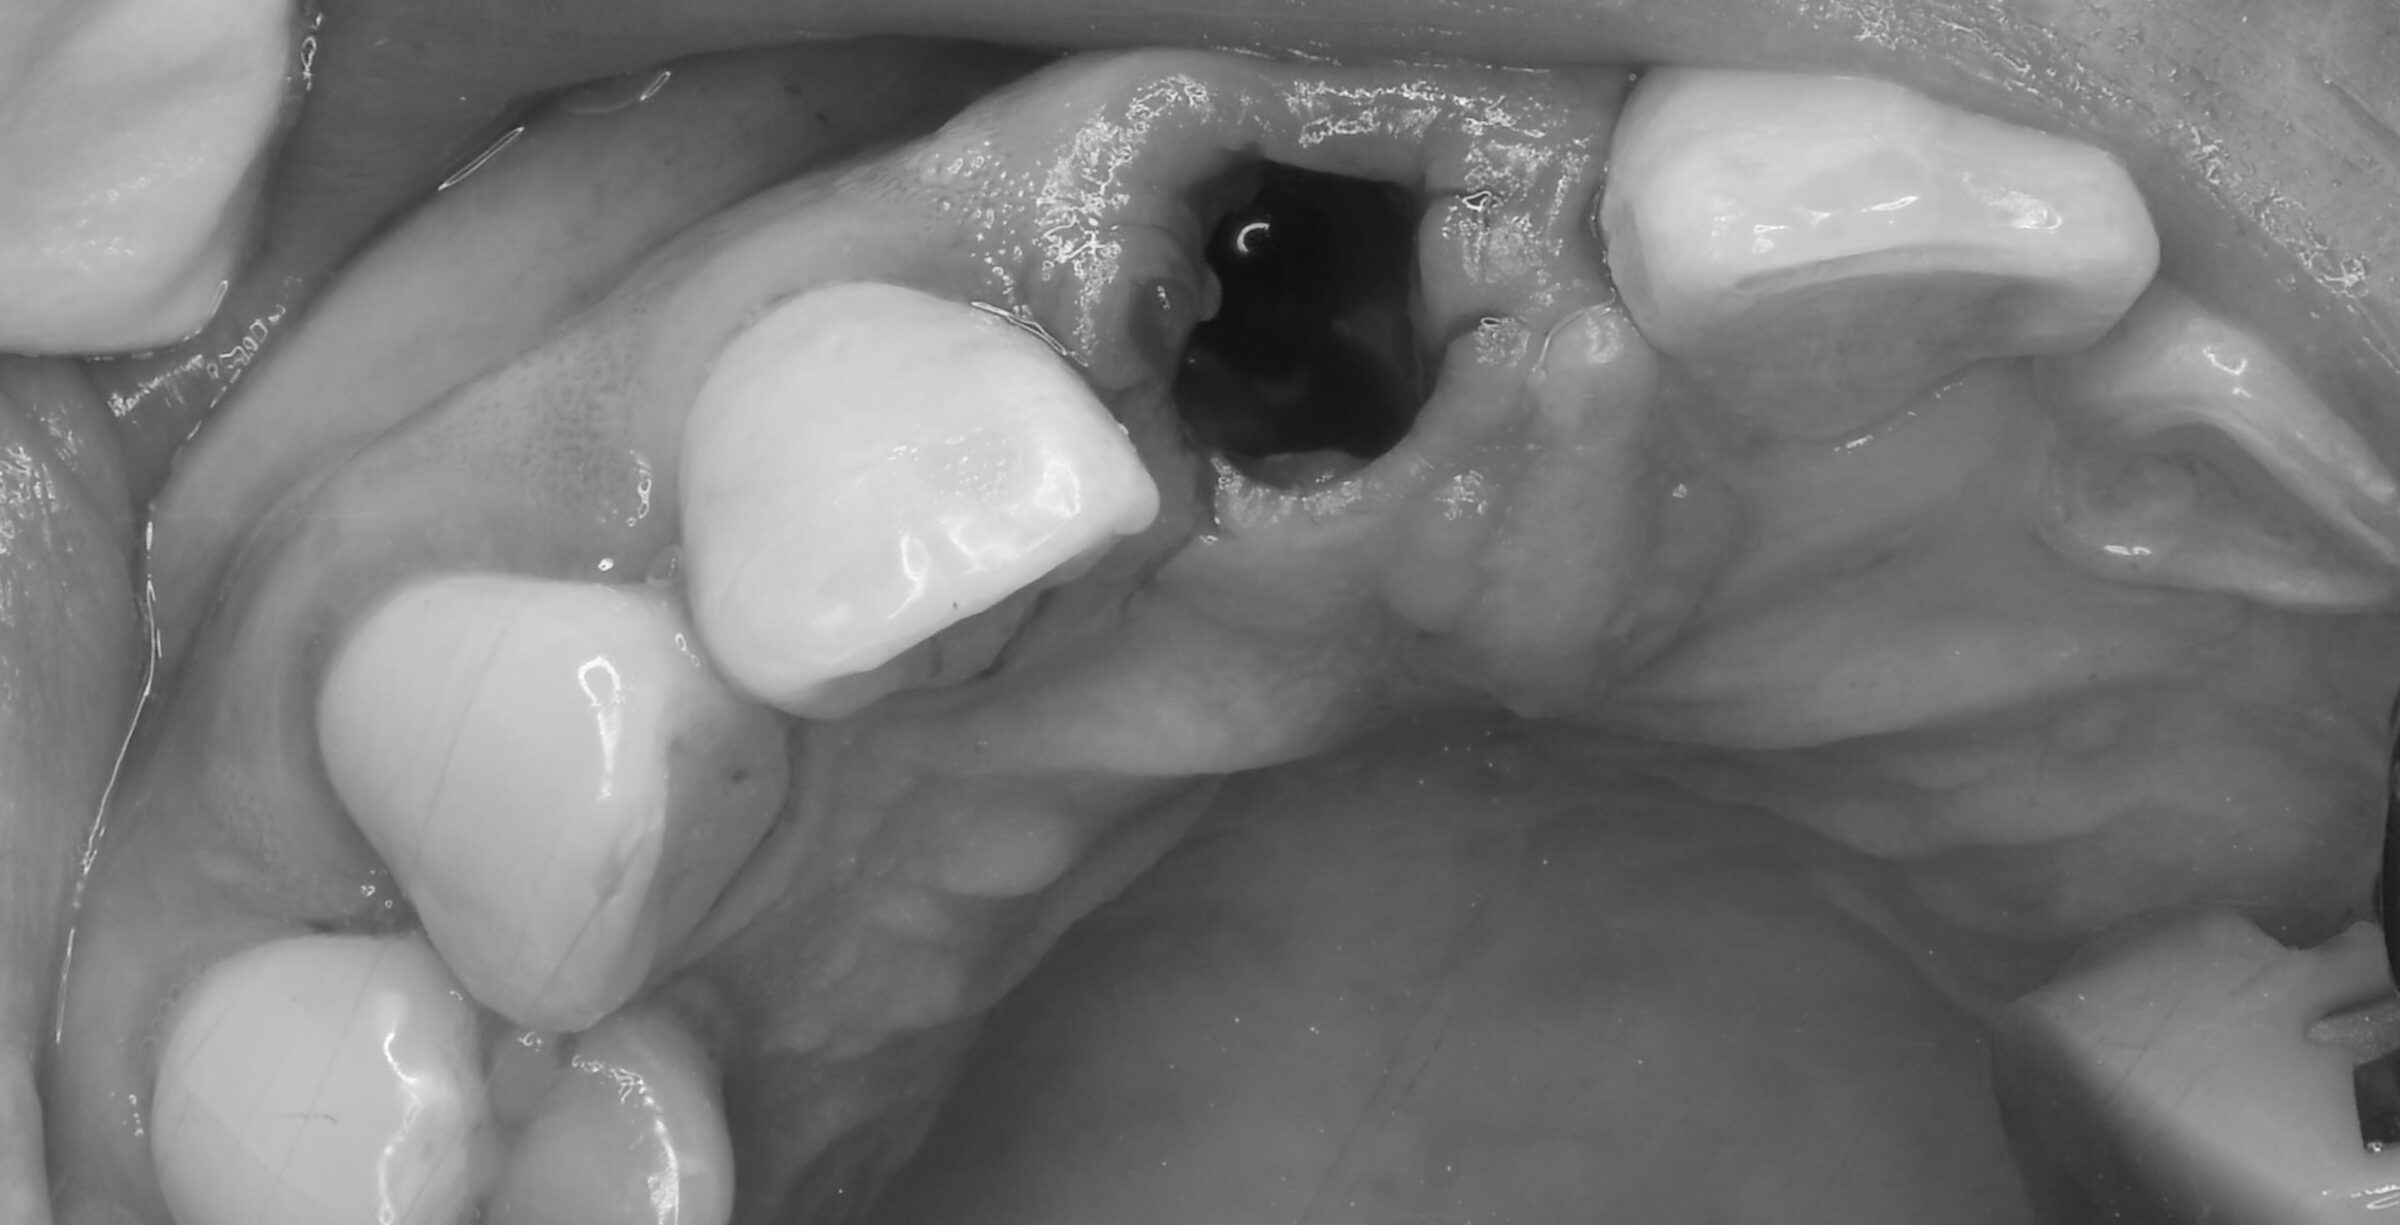

オペ中の口腔内写真